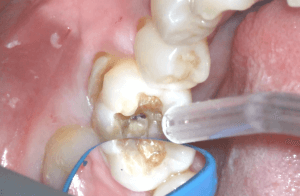

プラークの染め出し

歯垢(プラーク)はコンポジットレジン修復を行う上で歯との接着に悪影響を与えます。そのためきれいにしておく必要があるのですが、プラークは目に見えないものもあるため歯垢染め出し剤で歯を染め出してから除去しています。

こういった一つ一つの操作が接着を確実なものとする上でとても重要になります。